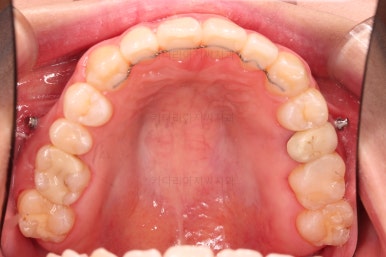

부산치아교정잘하는곳 키다리아저씨치과에서 치료를 종료했을 때의 사진입니다.

위아랫니가 가지런해졌고요.

다시 틀어지지 말라고 적절한 유지장치를 구성합니다.

보철 치아의 위치/크기로 인해 100% 중앙선은 맞기 힘드나 가장 잘 맞추어 놨고, 앞니의 각도도 매우 좋아졌습니다.

아래 앞니도 단순히 머리 부분만 뒤로 눕힌 것이 아니라 뿌리까지 뒤로 당겨왔고요.